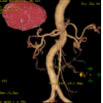

Abd Aorta MIP

显示腹部主动脉及其主要分支血管的起源.走形及其它的形态